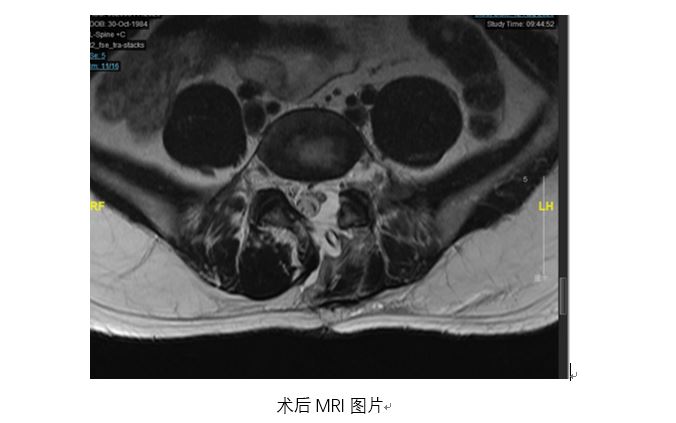

术中,赵杰主任带领手术团队,在为患者置入椎间孔镜时采用了腰椎后路微创手术切口同一入路,不给患者增加新的手术切口,不破坏关节突关节等脊柱结构,不广泛剥离椎旁肌软组织,不进行椎间融合钉棒固定,充分保证了患者要求的较高术后生活质量,巧妙实现了对正常骨结构的保护和对肿瘤的精准彻底切除。整个手术过程,骨科团队和神经外科团队配合流畅,术中神经电生理监测正常。

术后影像学提示患者关节突关节等骨性结构完整,术后病理回报肿瘤切缘干净,肿瘤切除彻底。患者腰腿痛症状明显改善,足部麻木感缓解。